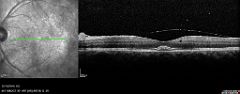

OCT 000 OCT 001 OCT 002 OCT 003

OCT 004 OCT 005 OCT 006 FA 000